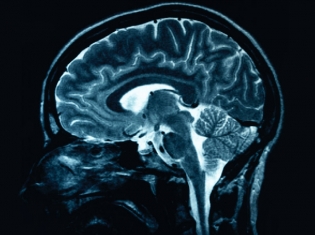

Strokes are one of the main causes of disability and death in adults. The mortality rate is especially high for those who suffer strokes involving brain hemorrhaging.

Working in the lab of Edward Feener, Ph.D., an associate professor of medicine at Harvard Medical School, researchers at the Joslin Diabetes Center discovered that plasma kallikrein obstructs the blood clotting process in the brains of rats with high blood sugar. When the researchers injected plasma kallikrein into the brains of rats with diabetes, they observed a dramatic increase in the level of bleeding compared to non-diabetic rats injected with the same protein. What's more, the researchers found that inhibiting the effects of plasma kallikrein in diabetic animals reduced the levels of bleeding.